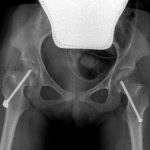

The surgical technique consists of inserting a cannulated screw into the femoral neck to prevent the femoral head from progressively move out of its natural socket.

The mean age of the patients was 7.5 years, with a range between 4 and 11 years. The radiographic assessment were performed in 4 phases: in the preoperative phase and 6, 12 and 60 months after surgery.

This was meant to to demonstrate the effectiveness of the intervention in maintaining the femoral head within the acetabulum.

In all the patients, surgery allowed to perfectly reach the goal of a total containment of the hip inside the acetabular socket persistent over the years.

In conclusion, it can be said that the temporary medial hemiepiphysiodesis of the proximal femur (TMH-PF) is an effective method of prevention and treatment for Developmental Dysplasia of the hip patients with Cerebral Palsy, avoiding or delaying major surgeries.